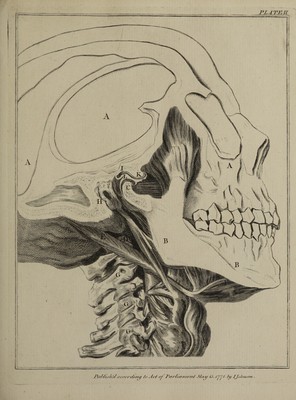

The natural history of the human teeth: explaining their structure, use, formation, growth, and diseases / By John Hunter.

- John Hunter

- 1778

Credit: The natural history of the human teeth: explaining their structure, use, formation, growth, and diseases / By John Hunter. Source: Wellcome Collection.